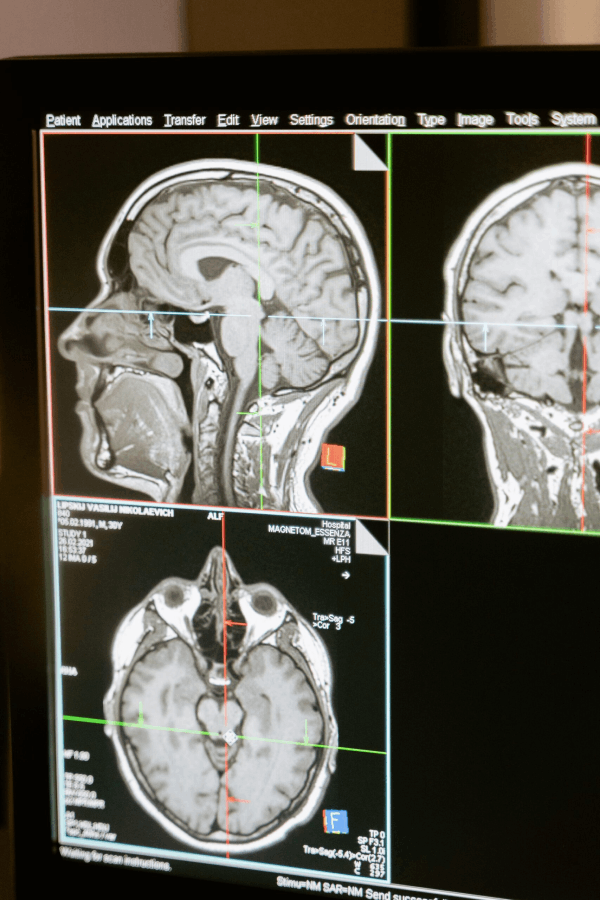

Neuropsychologische Diagnostik

Die neuropsychologische Diagnostik kommt v.a. nach einer Schädigung oder Erkrankung des Gehirns zum Einsatz. Dabei ist es möglich, kognitive und emotionale Funktionsstörungen zu diagnostizieren, um sodann mit einer effizienten und zielgerichteten Therapie zu beginnen.

- nach einer Hirnschädigung (Gehirnblutung, Schlaganfall, Gehirntumor)

- bei Erkrankungen des Zentralnervensystems (Demenz, Multiple Sklerose, Morbus Parkinson, Epilepsie)